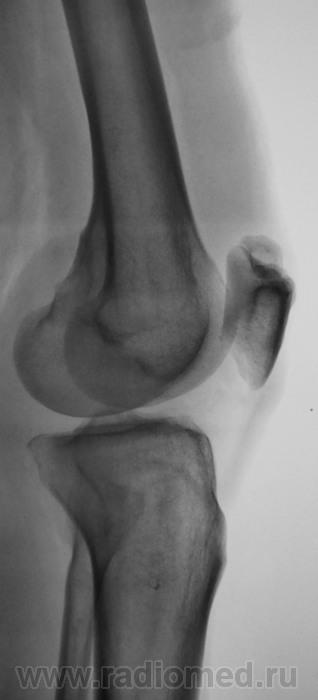

Травма. Направлен на рентгенографию коленного сустава

Несросшийся апофиз надколенника, деструкции не вижу

Без костных травматических изменений.

Такое развитие надколенника. Хотя может быть и травматический разрыв фиброзных сращений.

Подумала и решила исправить запись -исход остеохондропатии надколенника

А, может быть просто пателла бипарцита?

Можно уточнение ? Край основной массы надколенника неровный, углы заострены и щель выглядит неравномерной -это обычная картина при удвоении надколенника ?

И мне это не понравилось. И по боковой - впечатление о смещении фрагмента.

Мужчина 39 лет, жалоб нет. Обратил внимание на разницу с другим коленным суставом (выпирает). Второй сустав на снимке без изменений. Травм утверждает, что не было.